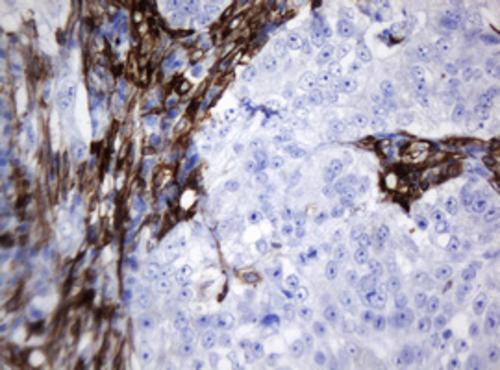

Immunohistochemical staining of paraffin-embedded Carcinoma of Human pancreas tissue using anti-TMEM173 mouse monoclonal antibody. (Heat-induced epitope retrieval by 10mM citric buffer, pH6.0, 120°C for 3min, BD-PE5636)